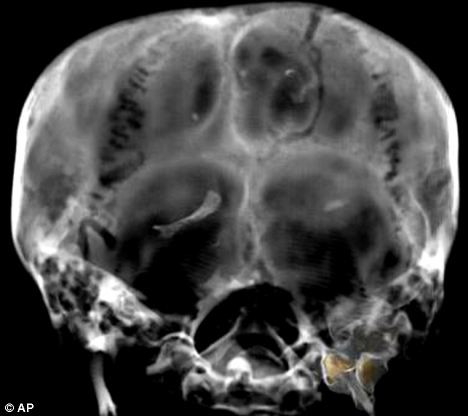

![]() |

| Hình ảnh hộp sọ vua Tut được quét cắt lớp chụp năm 2005 |

Các giả thuyết cho rằng ông bị ám sát vì là người cuối cùng cai trị triều đại và phía sau đầu của ông có một cái hố. Tuy nhiên, năm 2005, tiến sĩ Hawass tuyên bố rằng nhóm của ông đã không tìm thấy bằng chứng về cú đánh ở phía sau đầu và cái hố kia có từ quá trình ướp xác.